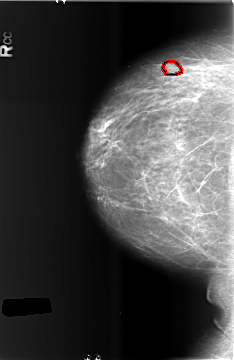

B_3432_1.RIGHT_CC

RIGHT_CC LINES 5752 PIXELS_PER_LINE 3736 BITS_PER_PIXEL 12 RESOLUTION 50 OVERLAY

FILE: B_3432_1.RIGHT_CC.OVERLAY

TOTAL_ABNORMALITIES 1

ABNORMALITY 1

LESION_TYPE MASS SHAPE OVAL MARGINS CIRCUMSCRIBED-OBSCURED

ASSESSMENT 4

SUBTLETY 3

PATHOLOGY BENIGN

TOTAL_OUTLINES 1